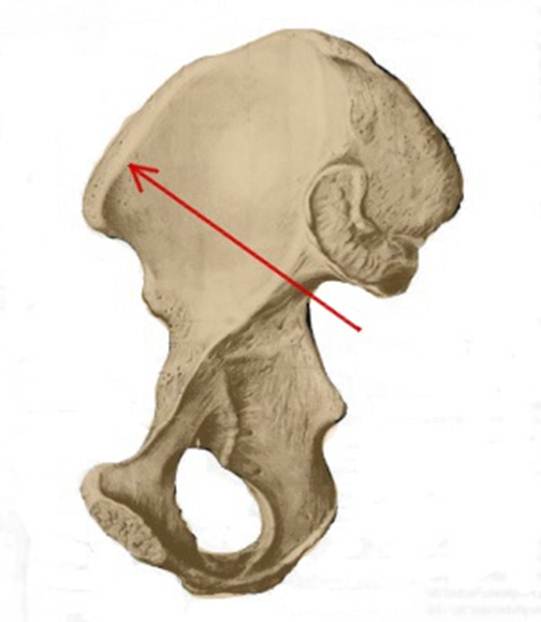

S: Стрелка указывает на os ilium (латинский язык).

S:Стрелка указывает на spina iliaca posterior superior

S:Стрелка указывает на lambium internum

S: Стрелка указывает на spina iliaca posterior inferior

S: Стрелка указывает на facies lunata (латинский язык).

S: Стрелка указывает на spina iliaca anterior inferior

S: Стрелка указывает на incisura ischiadica major

S: Стрелка указывает на spina iliaca anterior superior

S: Стрелка указывает на facies auricularis

S: Стрелка указывает на facies sacropelvica

S: Стрелка указывает на eminentia iliopubica

I:S: Стрелка указывает на spina iliaca anterior superior